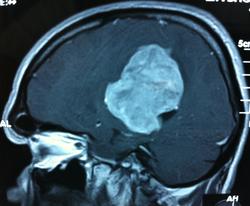

Начало вот здесь http://www.radiomed.ru/cases/kt-gms-obemnoe-obrazovanie-levoi-gemisfery-bolshogo-mozga-vnutrizheludochkovaya-meningioma. Пациент оперирован (меня сначала дезинформировали по поводу операции), перед операцией состояние ухудшилось, возникла правосторонняя гемиплегия, которая осталась и после декомпрессии. МРТ, КТ снимки и выписку предоставила супруга пациента, снимал на iphone, простите за качество, дисков с исследованиями не записывали. Надеюсь вопрос по данному случаю исчерпан.

Вот "цветочки":

T1+C

И Вы считаете, что эта опухоль имеет интравентрикулярную локализацию?

Изначально по КТ я так предпологал, а теперь на 100% уверен, разве МРТ это не показало? Гистологически - менингиома, опухоль мозговой оболочки. Покажите, пожалуйста, образование где-нибудь прилежит к костям, где есть мозговая оболочка? Я не вижу, зато отчетливо вижу в левом боковом желудочке из оболочек сосудистого сплетения. Что вас еще смущает? По-моему, предостаточно фактов, чтобы развеять все сомнения.

Мне видится так. Иначе в данной локализации просто неоткуда расти оболочечной опухоли. На контрольной КТ, после декомпрессии, когда срединные структуры стали действительно срединны, правое обызвествленное сосудистое сплетение видно отчетливо, а левое, где оно? Ведь если бы образование компремировало, то после операции, когда часть мозга пролабировало в трепанационное отверстие мы бы увидели и левое сосудистое сплетение, но оно интимно связано с образованием и даже "потянулось" за ним в сторону декомпрессионного отверстия, потому что это и есть "росток" откуда выросла опухоль.